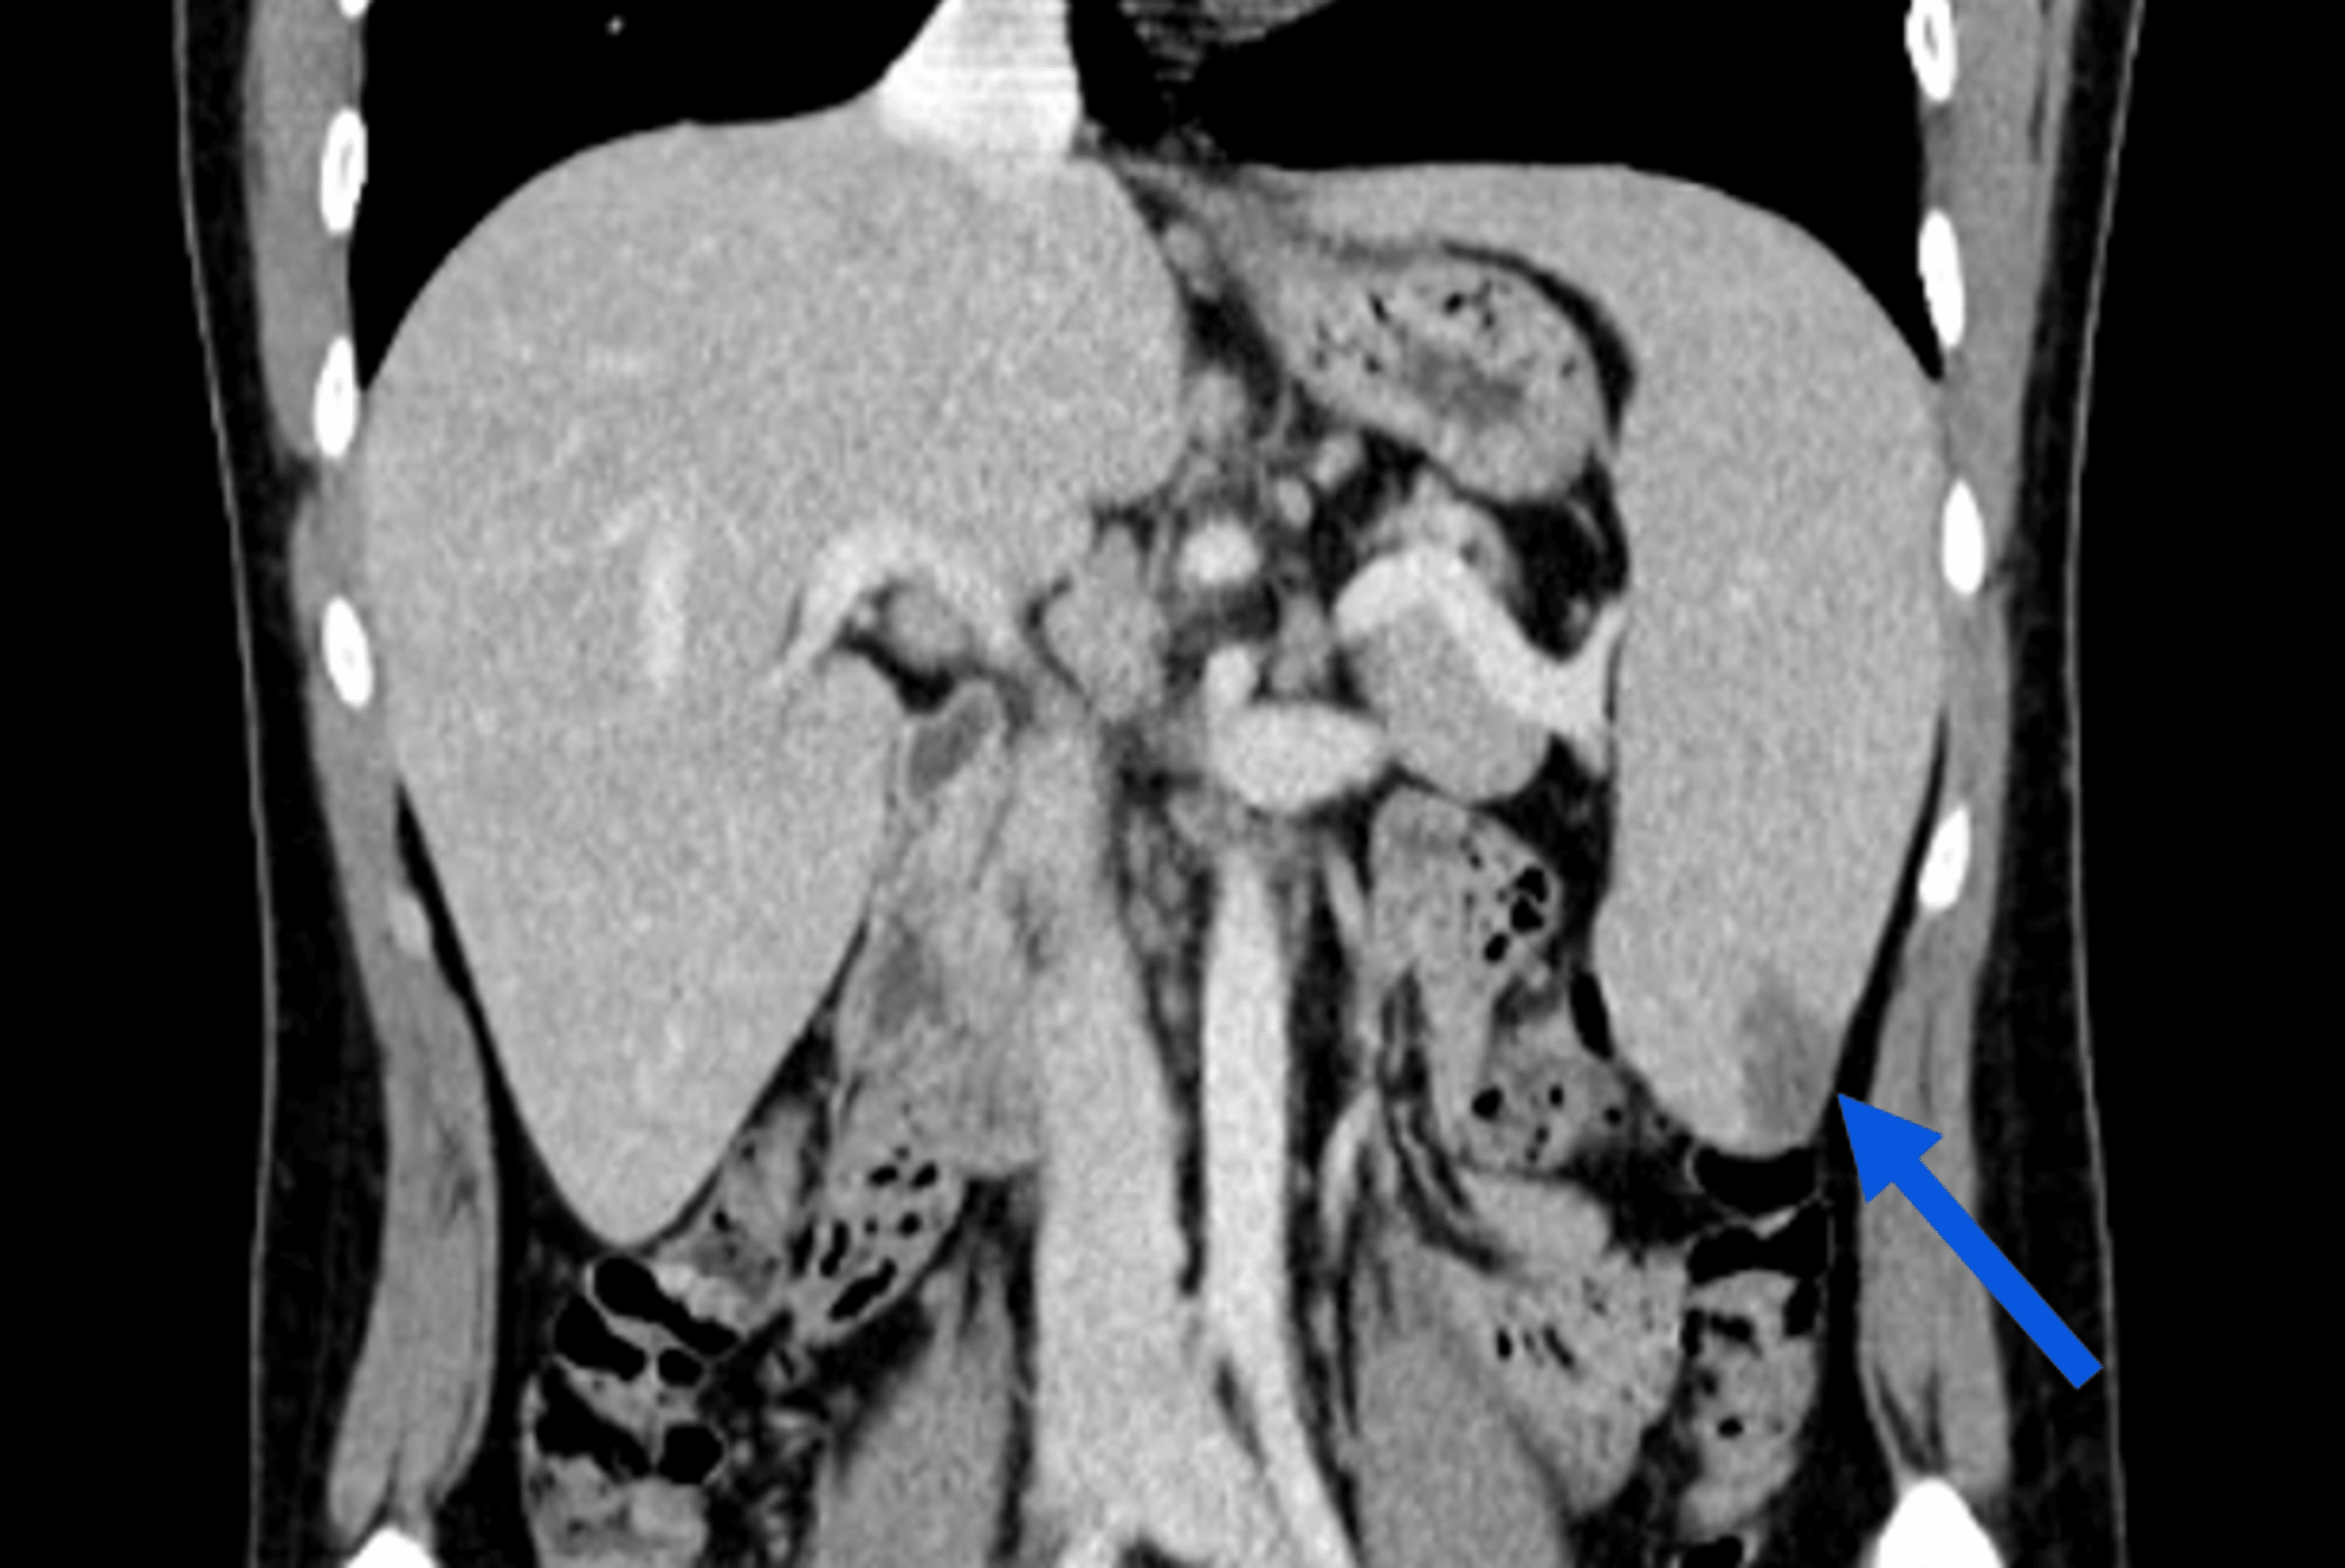

From www.eurorad.org

CT diagnosis of spontaneous rupture of spleen as the initial How Long Is Spleen Enlarged After Mono Depending on the severity of the illness, it’s possible that the person’s spleen may become enlarged. On average, it lasts six weeks. Let’s dive into how mono spreads, how to identify it, and how to treat. Enlargement of the spleen — the spleen is an organ in the left upper abdomen, just under the diaphragm (figure 1). The incubation period. How Long Is Spleen Enlarged After Mono.